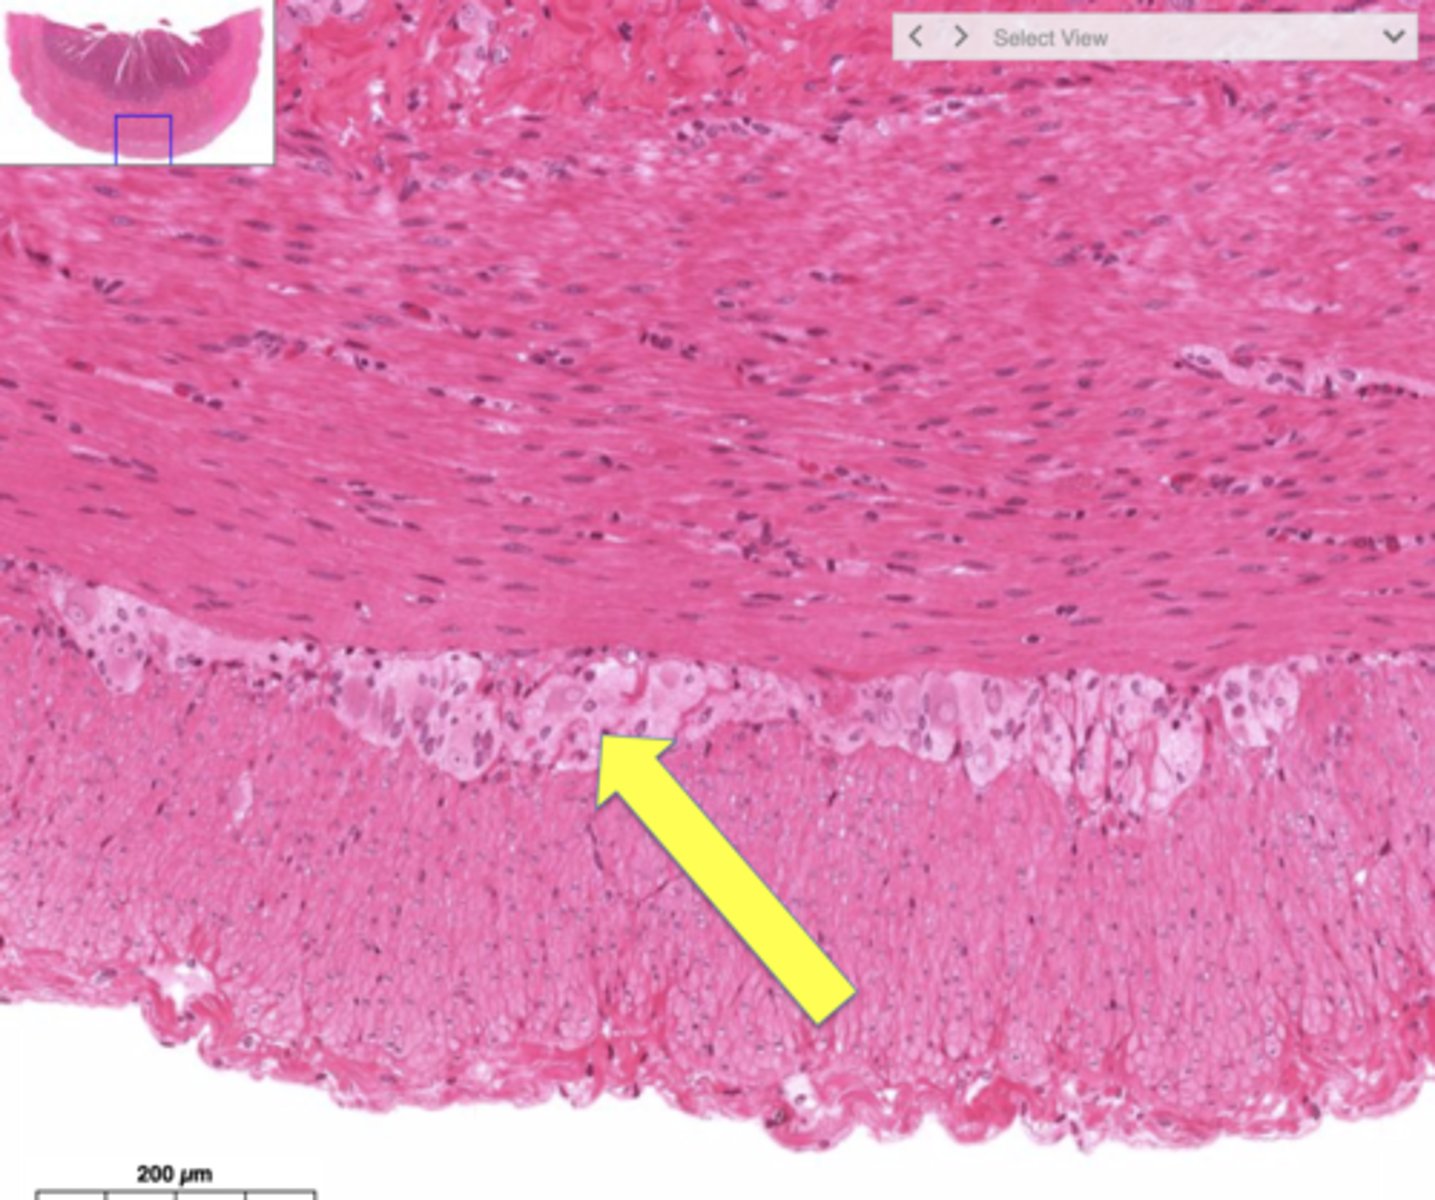

What is it called when an esophagus with normal squamous epithelium now has metaplastic columnar epithelium?

Barrett esophagus

What can result from an increased risk of dysplasia?

Esophageal adenocarcinoma

Jim is a 70 year old white man with GERD. He has had GERD for the past 6 years. You decide to screen him for Barrett's esophagus since he has two or more risk factors.

What test do you run?

What do you need to order to confirm the diagnosis?

What do you treat him with?

1.) Endoscopy

2.) Biopsy is needed for diagnosis

3.) Long-term PPIs once or twice daily to control reflux symptoms

Barrett's esophagus

What is this image of? It is salmon colored.